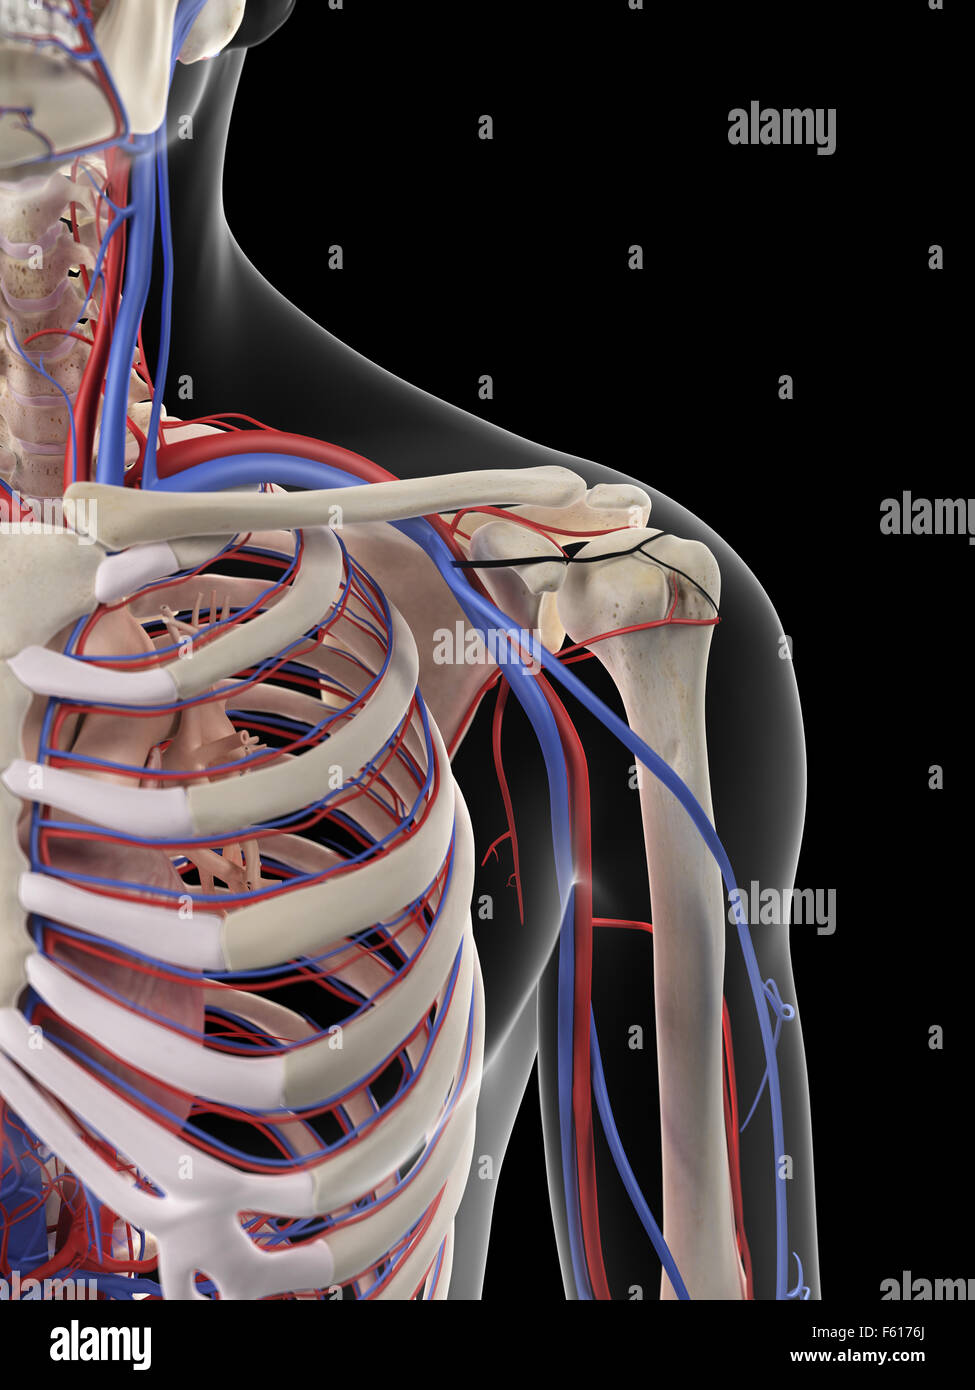

RMETMN27–Darstellung der Blutversorgung und Skelett-Struktur der Unterschenkel, durch die Haut sichtbar.

RMETMNMF–Darstellung der Blutversorgung und Skelettsystem an den Unterschenkeln, durch die Haut sichtbar.

RMETMP9E–Darstellung der Blutversorgung und Skelett-Struktur der Unterschenkel, durch die Haut sichtbar.